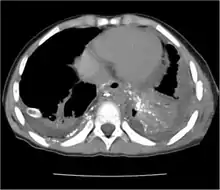

Chest X-rays can detect a chylothorax. It appears as a dense, homogenous area that obscures the costophrenic and cardiophrenic angles. Ultrasounds can also detect a chylothorax, which appears as an echoic region that is isodense with no septation or loculation. However, neither a normal chest x-ray nor an ultrasound can differentiate a chylothorax from any other type of pleural effusion.[1]

The cisterna chyli can be found in a thoracic MRI, making it possible to confirm chylothorax. However, MRI is not the ideal method to scan the thorax, and so it is rarely used. Another diagnostic technique is conventional lymphangiography. It is rarely used since there are equally sensitive yet less invasive techniques available to identify a chylothorax. Lymphangiography procedures use the contrast dye agent lipiodol, which is injected into the lymphatic vessels. The chylothorax shows up on the images and identifies the source any leak in the thoracic duct.[1]